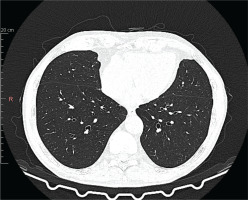

Figure 2

Chest high-resolution computed tomography after treatment with mepolizumab. Chest high-resolution computed tomography showing clear radiological improvement

A 65-year-old Caucasian male with a medical history of hypertension, prostatic hypertrophy, and duodenal ulcer disease was admitted to the pulmonology department for the evaluation of a persistent non-productive cough lasting approximately six months, alongside reported weight loss and decreased exercise tolerance. High-resolution computed tomography (HRCT) demonstrated peripheral ground-glass opacities with thickening of the interlobular septa, bilateral bronchial dilation, and small tumor lesions (Figure 1). Laboratory findings revealed significant eosinophilia in peripheral blood (53.8%) with leukocytosis (13.4 G/L). Diagnostic bronchoscopy with bronchoalveolar lavage (BAL) was performed, during which biopsies of papular lesions on the bronchial walls were taken. Bacteriological cultures, including testing for acid-fast mycobacteria and fungi, were conducted, revealing negative results for Aspergillus fumigatus antigens and antibodies. Histopathological examination indicated mild inflammation with a few eosinophils and no evidence of neoplasia. Cultures from the BAL fluid were also negative. To rule out common causes of eosinophilia, stool tests for parasites were performed, yielding negative results; however, antiparasitic treatment was initiated due to potential false negatives. An extensive autoimmune workup, including various autoantibody tests, returned normal results. Serological tests for atypical bacterial infections were conducted, with borderline results for Bordetella pertussis leading to treatment with clarithromycin; other bacterial infections were excluded. Echocardiography suggested cardiomyopathy, with further cardiac evaluations scheduled based on potential endocardial involvement. Given the pronounced eosinophilia, steroid therapy was initiated, resulting in a significant reduction in eosinophil levels to 1.3%. Three weeks later, BAL revealed that 85% of collected cells were eosinophils. Diagnosis of hypereosinophilic syndrome was established, and treatment with prednisone at 40 mg/day commenced. After one month, a follow-up chest radiograph indicated regression of peripheral nodular shadows and ground-glass opacities, with bilateral pericardial fibrosis. Pulmonary function tests revealed no abnormalities, and inflammatory markers in biochemical tests were negative, with no irregularities in the peripheral blood smear. Follow-up HRCT showed regression of interstitial changes. A decision was made to gradually reduce the prednisone dosage to 10 mg for 14 days, subsequently decreasing to 5 mg for another 14 days before cessation. Three months after stopping prednisone, eosinophilia re-emerged. Repeat bronchoscopy with BAL was performed, and a hematology consultation was scheduled to exclude clonal eosinophilia, which was ruled out, alongside cardiac MRI. Prednisone was reinstated at a maintenance dose of 5 mg/day, as attempts to taper led to recurrent eosinophilia. The patient exhibited a favorable response to treatment, with regression of radiological changes; however, treatment was complicated by recurrent infections. The patient continues to be monitored for any recurrence of infiltrates or eosinophilia upon dose reduction or discontinuation of glucocorticoids. No significant impairment of lung function was noted based on spirometry, body plethysmography, DLCO, and the 6-minute walk test. Secondary causes of eosinophilia were excluded, leading to a diagnosis of idiopathic chronic eosinophilic pneumonia. Due to the high risk associated with long-term systemic glucocorticoid therapy, a request for mepolizumab treatment was submitted and approved. Subsequent treatment with subcutaneous mepolizumab at 300 mg every four weeks commenced, with the goal of tapering or discontinuing systemic steroids. After two months, systemic steroid treatment was completely halted. Follow-up HRCT six months after starting mepolizumab showed improvement in interstitial and ground-glass opacities in both lungs (Figure 2). Follow-up laboratory work showed eosinophilia level 1.1%, WBC 4.7 G/L and CRP 1.0. He successfully weaned off steroids and has continued on mepolizumab 300 mg monthly dosing with maintained clinical improvement in symptoms. The patient has remained free of disease recurrence to date (over one year). The patient presents to the department every month for drug administration, during which routine laboratory tests are performed, including blood eosinophil level assessment (Figure 3). Additionally, the patient undergoes periodic chest X-ray examinations for monitoring purposes. The medication is well tolerated, and the patient reports no adverse effects. Furthermore, the patient reports an improvement in quality of life, with a decreased frequency of infections and no need for chronic corticosteroid therapy.